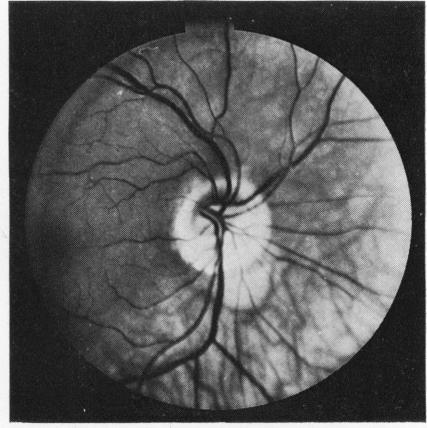

倾斜的视盘

The tilted disc.

Sixty tilted discs were studied by colour photography, including some by fluorescein angiography. Attention was drawn to the contracted, D-shaped outline of the scleral canal, and it was suggested that fewer fibres than normal enter the defective side of the disc. This was supported by examination of the nerve fibre layer and the discovery of field defects in 13 of the 27 eyes in which the visual fields were examined. The similarity of these features with congenital hypoplasia of the optic nerve head was noted.

通过彩色摄影对60个倾斜视盘进行了研究,其中一些还进行了荧光素血管造影。人们注意到巩膜管呈收缩的D形轮廓,并提出进入视盘缺陷侧的纤维比正常情况少。对神经纤维层的检查以及在接受视野检查的27只眼中的13只眼中发现视野缺损支持了这一观点。还注意到这些特征与视神经乳头先天性发育不全的相似性。